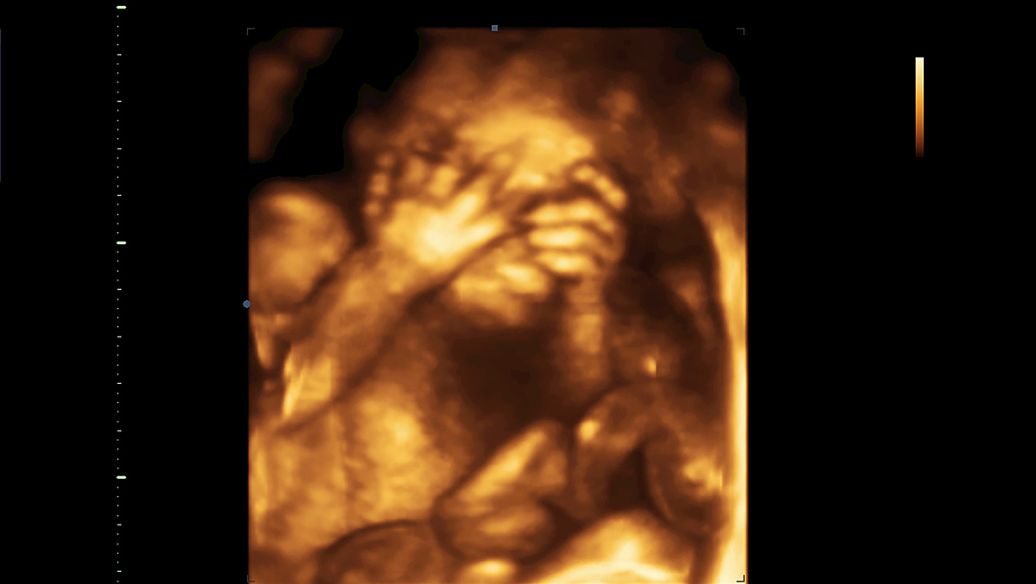

怀孕第28周

第28周-胎儿体重已有1100~1400克,坐高约为26厘米,几乎已经快占满整个子宫空间。胎儿的眼睛能够开合,已形成了自己的睡眠周期。此时胎儿经常会把自己的大拇指或其他手指放到嘴里去吸吮。